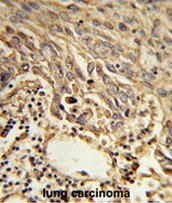

Supportive validation

- Submitted by

- OriGene (provider)

- Main image

- Experimental details

- Formalin-fixed and paraffin-embedded human lung carcinoma reacted with EIF4A2 Antibody (C-term), which was peroxidase-conjugated to the secondary antibody, followed by DAB staining. This data demonstrates the use of this antibody for immunohistochemistry; clinical relevance has not been evaluated.

- Validation comment

- IHC